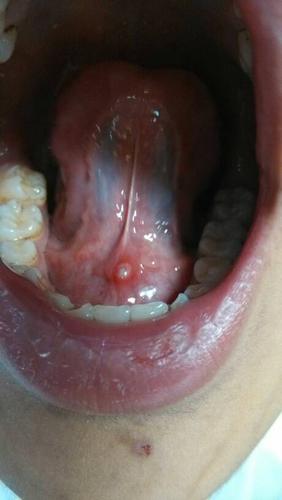

舌头下面长这个东西,很疼,这是什么?

请问舌头上的这个东西是什么,我大约七八岁就有这个东西了,当时只是一

舌头下面长了个小肉芽

舌头下长肉芽图片说明

舌头底下长肉芽图片

艾滋病舌头长肉芽图片

舌癌初期肉芽图片

舌头底下长疣体图片